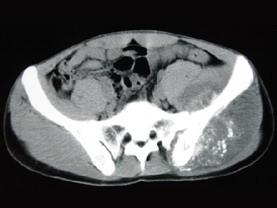

问题 男,35岁,左髂部剧烈疼痛,尤以夜间明显,可摸到肿物,请结合所提供图像,选择最佳选项 ( )

选项 A、骨肉瘤 B、软骨瘤 C、软骨肉瘤 D、骨转移瘤 E、骨巨细胞瘤

答案 A